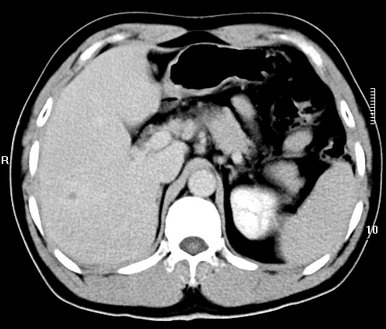

标题: CT19720:肝右叶血管瘤。肝左叶内侧段病灶考虑什么? [打印本页]

标题: CT19720:肝右叶血管瘤。肝左叶内侧段病灶考虑什么?

男,48岁,肝区不适月余,伴隐痛。

支持右叶血管瘤,左叶病灶考虑肝腺瘤。

1)不排除肝左叶肝癌。2)肝右叶血管瘤。

肝左叶炎性病变,肝癌待排。2)肝右叶血管瘤。

1.肝右叶血管瘤;2.肝左叶炎性假瘤?肝癌?建议穿刺活检.

右叶病灶典型,左叶病变慢性炎块

1、肝右叶血管瘤(典型)。

2、肝左叶病灶,强化不明显,疑炎性假瘤,建议结合临床并密切随访。

1、肝左叶炎性病变,肝癌待排。

2、肝右叶血管瘤。

肝左叶脓肿,肝癌待排。2)肝右叶血管瘤